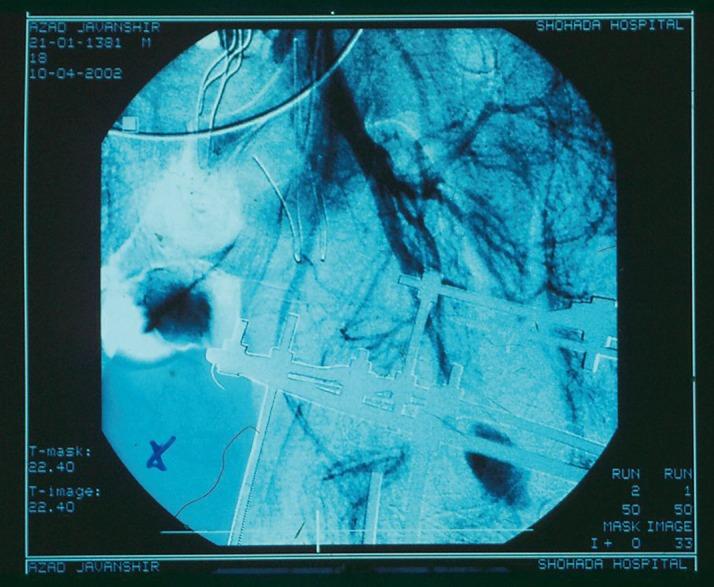

Pseudoaneurysms (PSA) of deep femoral artery (DFA) have been reported following penetrating and blunt trauma to the thigh and orthopedic procedures of the proximal femur. We describe a case of pseudoaneurysm of DFA as a late complication of limb trauma which was confirmed by exploration in an urgent surgery. After two operations successful surgical repair was performed.

https://cdn.ncbi.nlm.nih.gov/pmc/blobs/a428/3860639/3c2b037c88c2/traumamon-17-305-g001.jpg